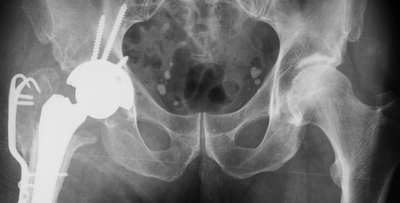

[Ortho] Клинический разбор пациентки с ложным суставом шейки правой бедренной кости

Имя     : 2.12.13 small.JPG

Url     : http://weborto.net:8080/pipermail/ortho/attachments/20160219/e0faf22a/attachment-0003.jpeg